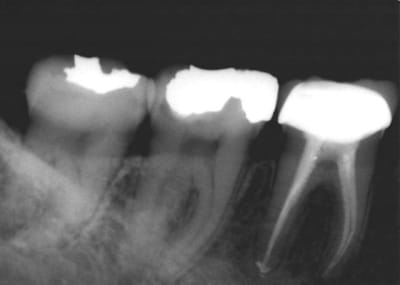

Allez pour parler un peu du quotidien, un cas d'endo qui date d'un petit moment, que feriez vous ?

Couronne, pas couronne ?

Ca a été fait sous digue et c'est du niti pur sucre en ML...

Onlay ou couronne (impossible de dire sans évaluer les pertes de substances exactes, ce que ne permet pas la retro).

on semble voir sur le distal un début de lésion. peut être que malgré ton geste plutôt bien réalisé l'irrigation n'aie pas été suffisante. SI tu avais un débût de nécrose.

POur ton ni ti il semble qu'il y aie une sortie commune donc pas de souci.

La première radio du post était de 2006, c'était une bio classique, pas de nécrose, grosse carie juxta pulpaire.